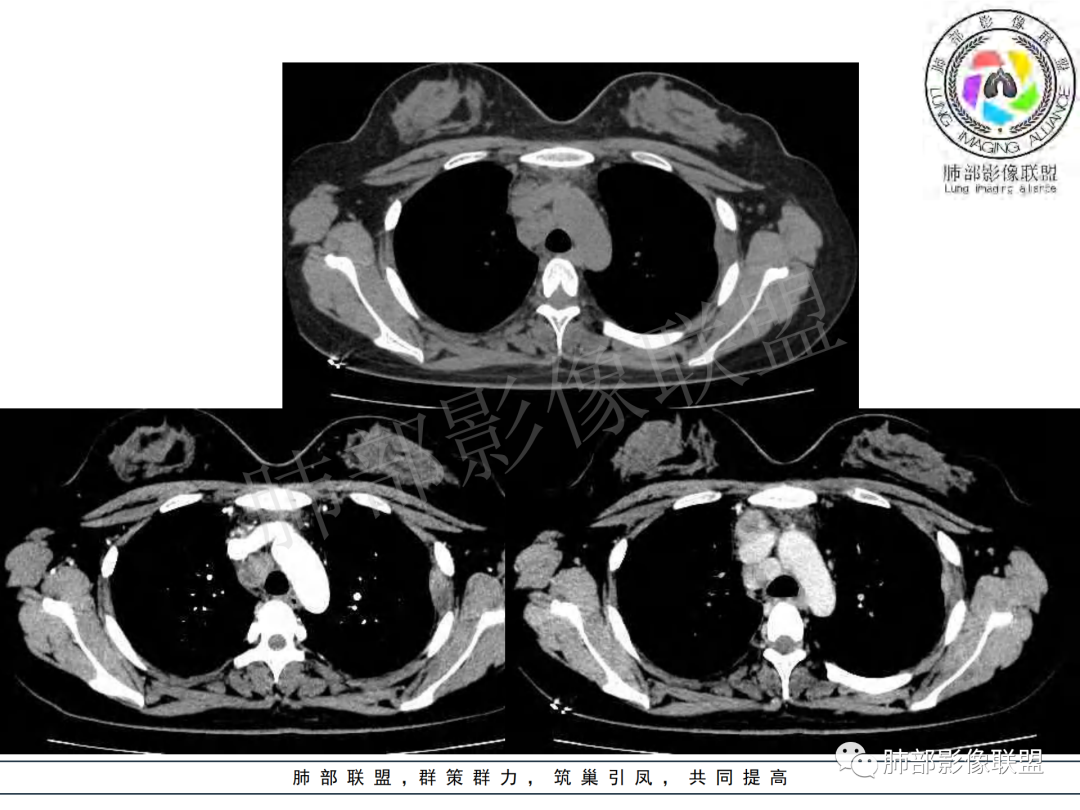

右肺肺门旁肿块,右肺中间段支气管腔内结节,增强强化不均;纵隔多发淋巴结环形强化,右侧少量胸腔积液,临床发热入院,考虑结核,鉴别肿瘤。

纵隔多组及右侧肺门多发肿大淋巴结,部分融合,不均匀强化,内见斑片状坏死区及环状强化,后者坏死边界尚清晰,肺门区肿大淋巴结与肺组织边界不清,年轻女性,8个月病史,发热首发症状,考虑淋巴结核并向肺内侵及(破溃?),鉴别淋巴瘤

女,20,病程长达8月,发热、胸痛、右侧胸腔积液病史。胸部CT:右肺门旁不规则肿块影,右中间支气管腔内结节,纵隔多发淋巴结肿大;强化不均匀,灶性坏死灶,环形强化;右侧少量胸腔积液并局部肉芽肿样突起。年轻女性,长病程,多部位,考虑慢性炎症,结核?鉴别肿瘤。

青年,右肺门增大,见软组织肿块影,部分支气管腔结节,并管腔狭窄,增强后明显不均匀强化,伴纵隔多发肿大淋巴结,环形强化,考虑恶性,类癌,鉴别支气管内膜结核

右肺门不规则肿块,向气管腔内生长,不均匀强化,其内粘液栓,纵隔淋巴结增大,部分有坏死,胸膜结节强化,考虑恶性,粘表?类癌?鉴别结核

年轻女性,慢性病程,发热、胸痛。右肺门旁不规则肿块影,纵隔多发淋巴结肿大;强化不均匀,环形强化;右侧少量胸腔积液;首先考虑结核,鉴别肿瘤,结节病。

年轻女性 大支气管占位恶性三件套 高强化 内部可见无强化区,无强化区与强化区内边界大部分不清晰,类癌、粘表、腺样囊性癌。首先考虑粘表   其次需要鉴别的有结核   这么大片的坏死 结节病可能性小

青年女性,发热、胸痛、右侧胸腔积液病史,病程8个月。曾多次抗炎后均有好转。CT:右肺门旁肿块影,双侧胸膜结节,纵隔多发淋巴结肿大,边缘模糊;增强渐进性明显强化,纵膈淋巴结较彻底坏死灶,边缘环形强化。考虑结核,鉴别恶性肿瘤。

女性,20岁。高热、畏寒。右肺上叶近肺门区不规则肿块,周围斑点、片小结节影伴肿大淋巴结,肿块包绕并突入右主支气管腔内,增强后肿块不均匀强化,淋巴结环形强化中心低密度,考虑结核。

纵隔肺门及两侧胸膜强化结节,支气管管腔不通畅。结核能解释临床及影像,就是强化有点猛,这个妖怪真不好说。恶性如类癌/高级别黏表/恶性间皮也要考虑。

本例患者,年轻女性,慢性病程,多次抗感染治疗效果不佳,实验室检查示白细胞及中性粒细胞不高,不支持普通细菌感染,虽然肺泡灌洗液X-Pert检测阴性,结合患者胸部CT结核感染亦不能排除,胸部CT主要表现为右侧肺门及纵隔淋巴结肿大,仔细观察不难发现右中间支气管内新生物凸向管腔内,增强扫描,右肺门(10R)及纵隔淋巴结(2R,4R)明显不均匀强化,内部呈不规则低密度无强化区,被周边高强化区包绕(环形强化)的特点,首先应当想到纵隔淋巴结结核诊断。淋巴结分布亦不符合肺部恶性肿瘤迁徙途径。